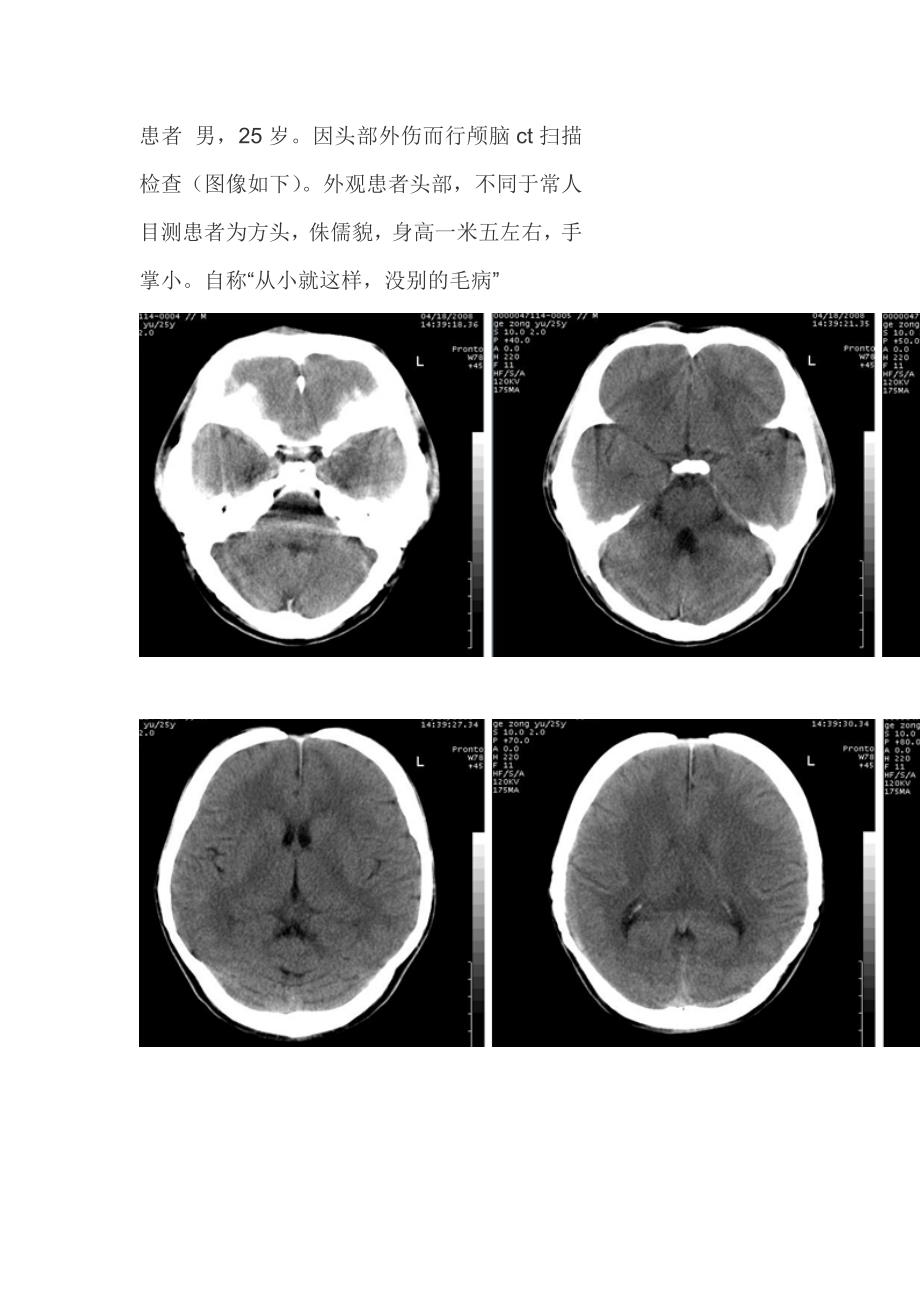

患者 男,25 岁因头部外伤而行颅脑 ct 扫描检查(图像如下) 外观患者头部,不同于常人目测患者为方头,侏儒貌,身高一米五左右,手掌小自称“从小就这样,没别的毛病”结果:颅锁骨发育不全颅锁骨发育不全(cleidocranial dysostosis),也称颅锁骨发育异常(cleidocranial dysplasia)、骨-牙形成障碍,为全身性骨发育障碍,属常染色体显性遗传半数以上病例有家族史,是骨发育异常中较常见的疾病 患儿常在出生时就被注意到头颅软和锁骨发育异常也可在发程中,因前额增宽或体型小而引起父母注意颅骨缺陷导至短头畸形,以额为著,常在中央有一夭状沟因锁骨缺如或发育不良致双肩下垂,并能靠拢于胸前乳牙萌出和脱落延迟,拔乳牙不能萌出常因听小骨的结构异常伴岩骨和乳突的致密硬化而致听力下降病人身材矮小四肢及指(趾)短小,脊柱侧弯智力发育正常。